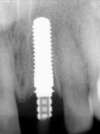

La planification est réalisée par ordinateur.

La dent sera enlevée et l'implant est positionné dans le même temps, une empreinte est réalisée et la prothèse provisoire sera posée le soir même.